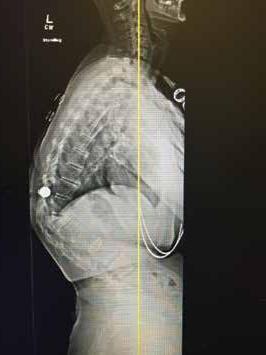

Total disc replacement (TDR) may be an alternative to spinal fusion for patients with cervical or lumbar herniated discs or degenerative disc disease.

The goals of total disc replacement surgery are to maintain segmental spinal motion, relieve pain, increase activity, restore disc height and proper spine curvature, and reduce post-operative recuperation time.

If you are experiencing neck or back pain and are considering surgery, isn't it worth your time to schedule an appointment with Dr. Jason E. Garber to nd out if motion preservation technology is an option for you?

Dr. Garber is one of Southern Nevada's most experienced spinal surgeons and a leader in arti cial disc replacement surgery.